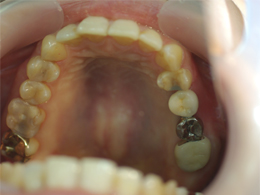

奥歯は骨が少なく、骨をつくり、インプラント治療をしました。赤く囲ったところが出来た骨です。